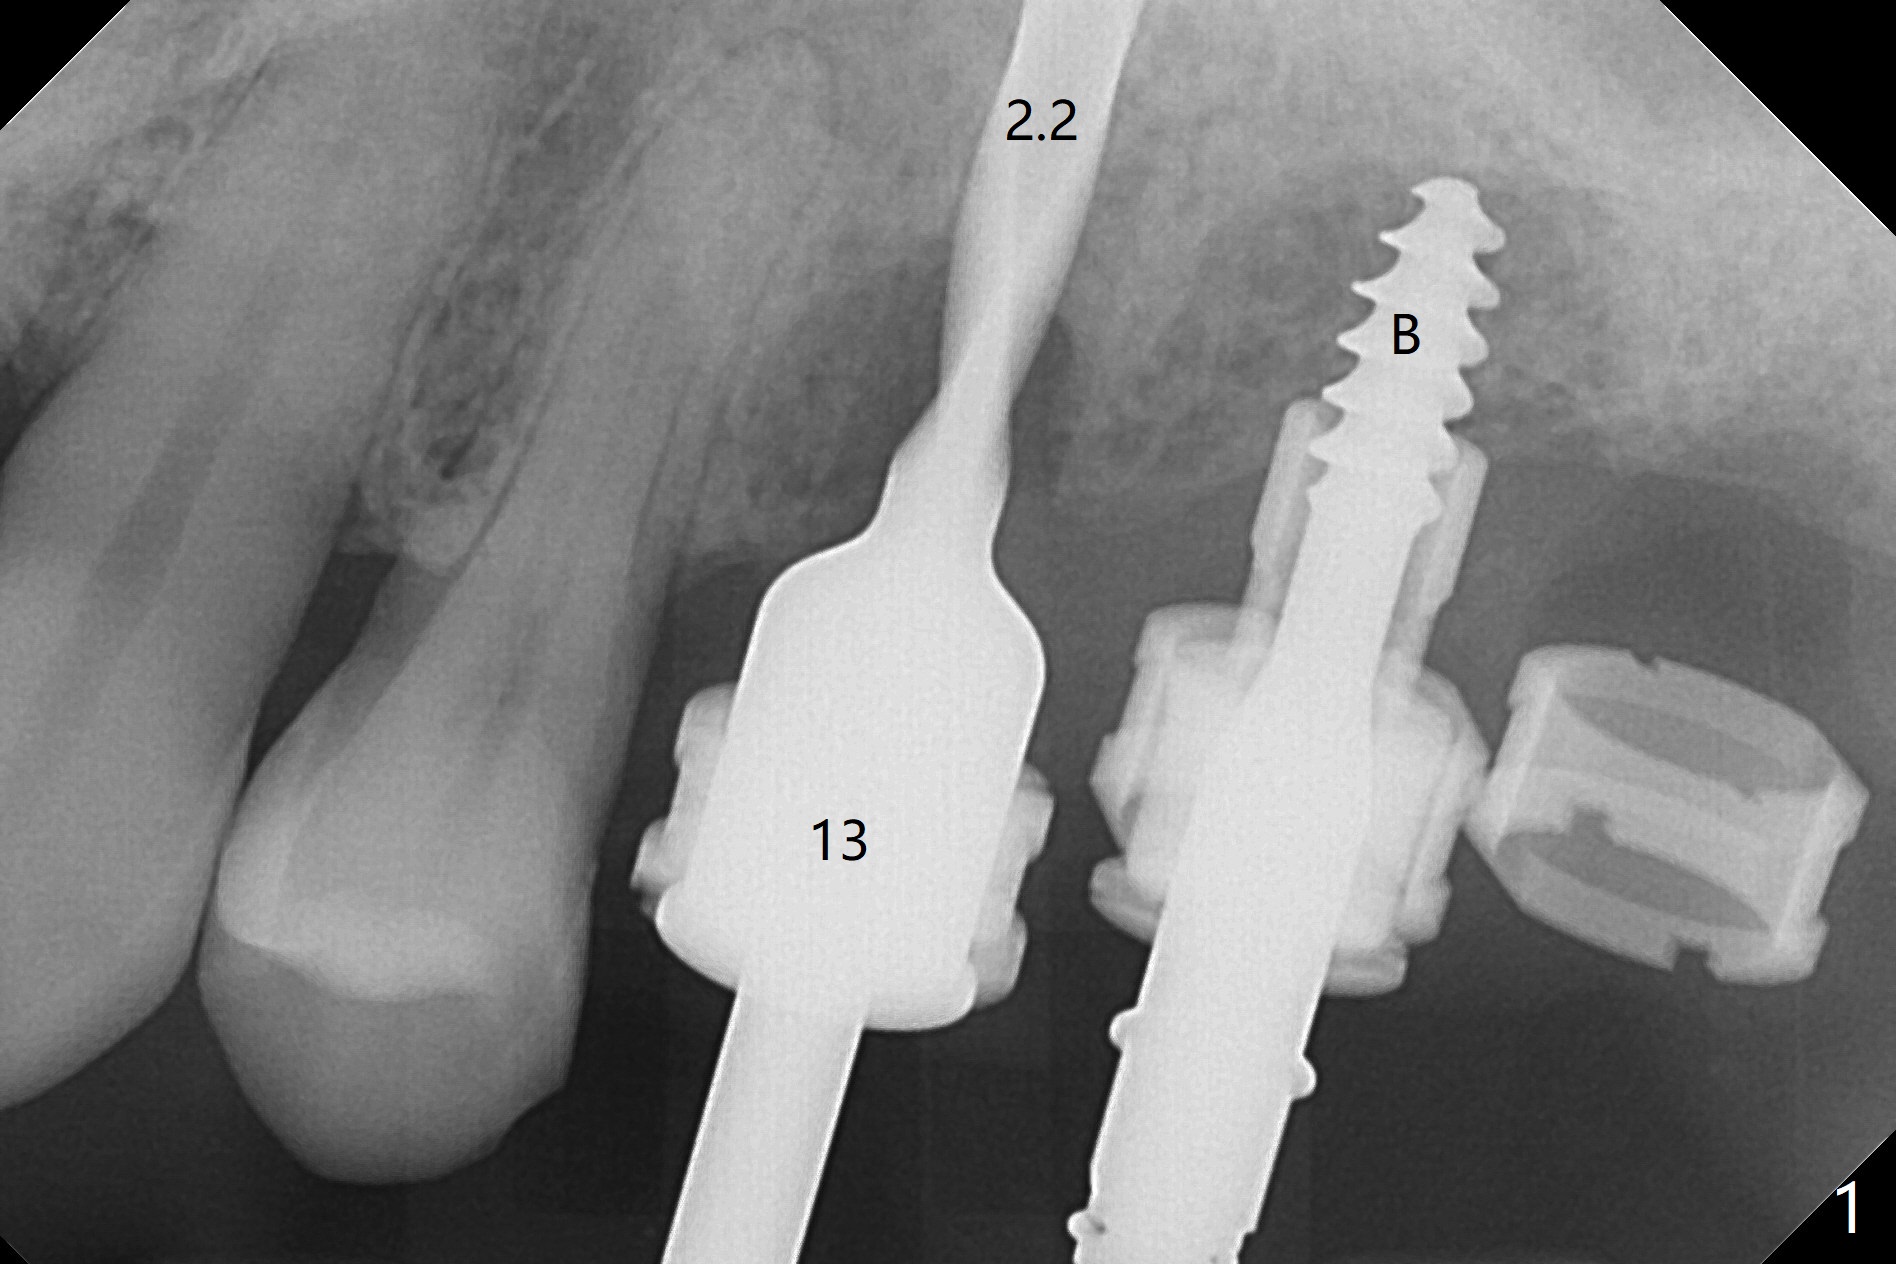

Extraction of abutment teeth associated with the loose FPD is not as easy as expected. Bony anchor placed at #14 (Fig.1 B) becomes loose while initial osteotomy a 2.2 mm drill at #13 for trajectory confirmation. The sinus membrane perforates at #15 when the sinus probe is being used. Luckily the perforation appears to be repaired with 2 pieces of PRF; sinus lift is assisted with a 4.5x10 mm dummy implant (Fig.2 *). Sinus lift at #14 is difficult and incomplete because of small osteotomy (Fig.3,5). In fact there is no sinus infection postop. Splinted immediate provisional is fabricated, but should be sectioned for individual units to form gingival scallops with distinct papillae. Three months postop, the splinted provisional is removed. The abutment at #14 is supragingival and is changed to 4.5x7(3) mm one. Individual temporary crowns are fabricated. Two weeks later, a small papilla forms between #14 and 15, while the temp at #13 is lost. The abutment at #13 changes to 4.5x7(5) mm one (Fig.7) with a new provisional, whereas those at #14 and 15 relined. In fact the abutment at #15 is incompletely seated (<) probably related to contact with the mesial crest (*). An abutment with smaller diameter and longer cuff at #15 seems to be completely seated (Fig.8,9, as compared to Fig.7). Following screw torque at 30 Ncm, impression is taken.